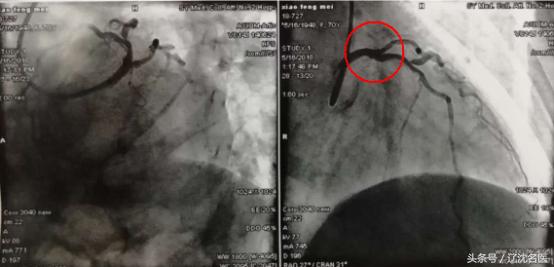

术中,先后用4跟导丝顺利开通左主干和前降支,植入支架一枚,40分钟结束手术!

术后